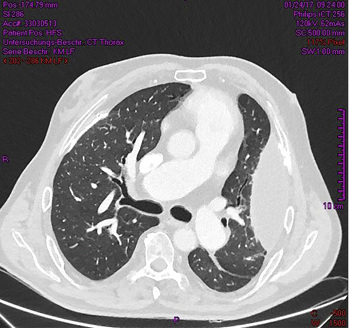

Im Rahmen der Abklärung des chronischen Hustens wurde im Januar 2017 beim Pneumologen eine Röntgen-Untersuchung des Thorax in zwei Ebenen angefertigt. Dabei zeigte sich im p.-a.-Bild in Projektion auf die linke Thoraxwand eine große, in die Lunge hineinragende, gekammerte Raumforderung (  Abb. 1a ). Der linke phrenicocostale Winkel war verklebt. Die rechte Zwerchfellkuppe war nicht glatt begrenzt. Die Lungenhili kamen deutlich vergrößert zur Darstellung. Das Mediastinum war leicht nach links verlagert. Rechtsseitig zeigten sich Kerley-B-Linien. Sternal lagen Cerclagen bei Z.n. Sternotomie. In der seitlichen Aufnahme waren deutliche Pleuraverkalkungen im Bereich der Zwerchfellkuppe erkennbar (  Abb. 1b ).

Im kurz darauf angefertigten Computertomogramm des Thorax zeigten sich massive pleurale Verkalkungen, die teilweise tafelbergartig konfiguriert waren (  Abb. 3 und 4 ). Die Plaques fanden sich lateral auf beiden Thoraxseiten, paravertebral rechts mit krähenfußartigen Ausziehungen sowie an typischer Stelle auf der Zwerchfellkuppe. Links lateral war eine breitflächig gekammerte pleurale Flüssigkeitsansammlung zu sehen. Im nach links verlagerten Mediastinum zeigten sich ein schmaler Mediastinalerguss rechts, eine Aufweitung der Arteria pulmonalis sowie eine Kaudalverlagerung des linken Pulmonalissegments. Der rechte Vorhof war vergrößert. Nebenbefundlich fiel ein Gallenblasenkonkrement auf.

In dem vorliegenden Fall wurden mit einer Latenz von 44 Jahren nach letzter beruflicher Asbestexposition erstmalig als Zufallsbefund Veränderungen der Pleura festgestellt. Aufgrund der Röntgendiagnostik konnten Verkalkungen und ein Erguss nachgewiesen werden. Darüber hinaus waren beginnende Veränderungen des Lungengerüsts erkennbar. Durch die Punktion des Ergusses konnten die bestehende Herzerkrankung und die rheumatische Arthritis als Ursachen ausgeschlossen werden. Ebenfalls wurde ein Mesotheliom ausgeschlossen. Somit ist eine Asbestpleuritis bei benignem Pleuraerguss wahrscheinlich. Zudem zeigte sich in der Verlaufskontrolle das erneute Auftreten des Ergusses. Die Lungenfunktionsdiagnostik, die bei vorhandenem Erguss durchgeführt wurde, ergab gemäß Leitlinie Spirometrie (2015, s. „Weitere Infos“) noch einen Normalbefund, so dass derzeit kein Therapiebedarf bestand.